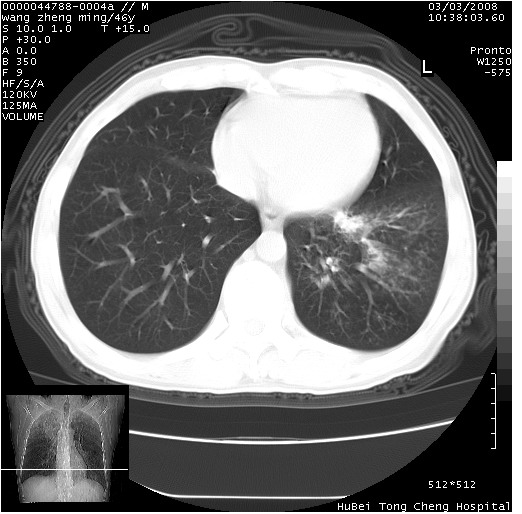

以下是引用卜一在2008-3-22 1:37:00的发言:[br]右肺实质性肿块,边缘不整,明显见毛刺征 分叶征及胸膜凹陷征,右上叶支气管明显变窄,远端散在的片状 斑片状实变影。另:左肺门较大肿块,支气管受累 变窄,远侧见阻塞性肺炎。纵隔内见肿大淋巴结。多考虑:右肺周围性肺癌伴左肺门 纵隔淋巴结转移!